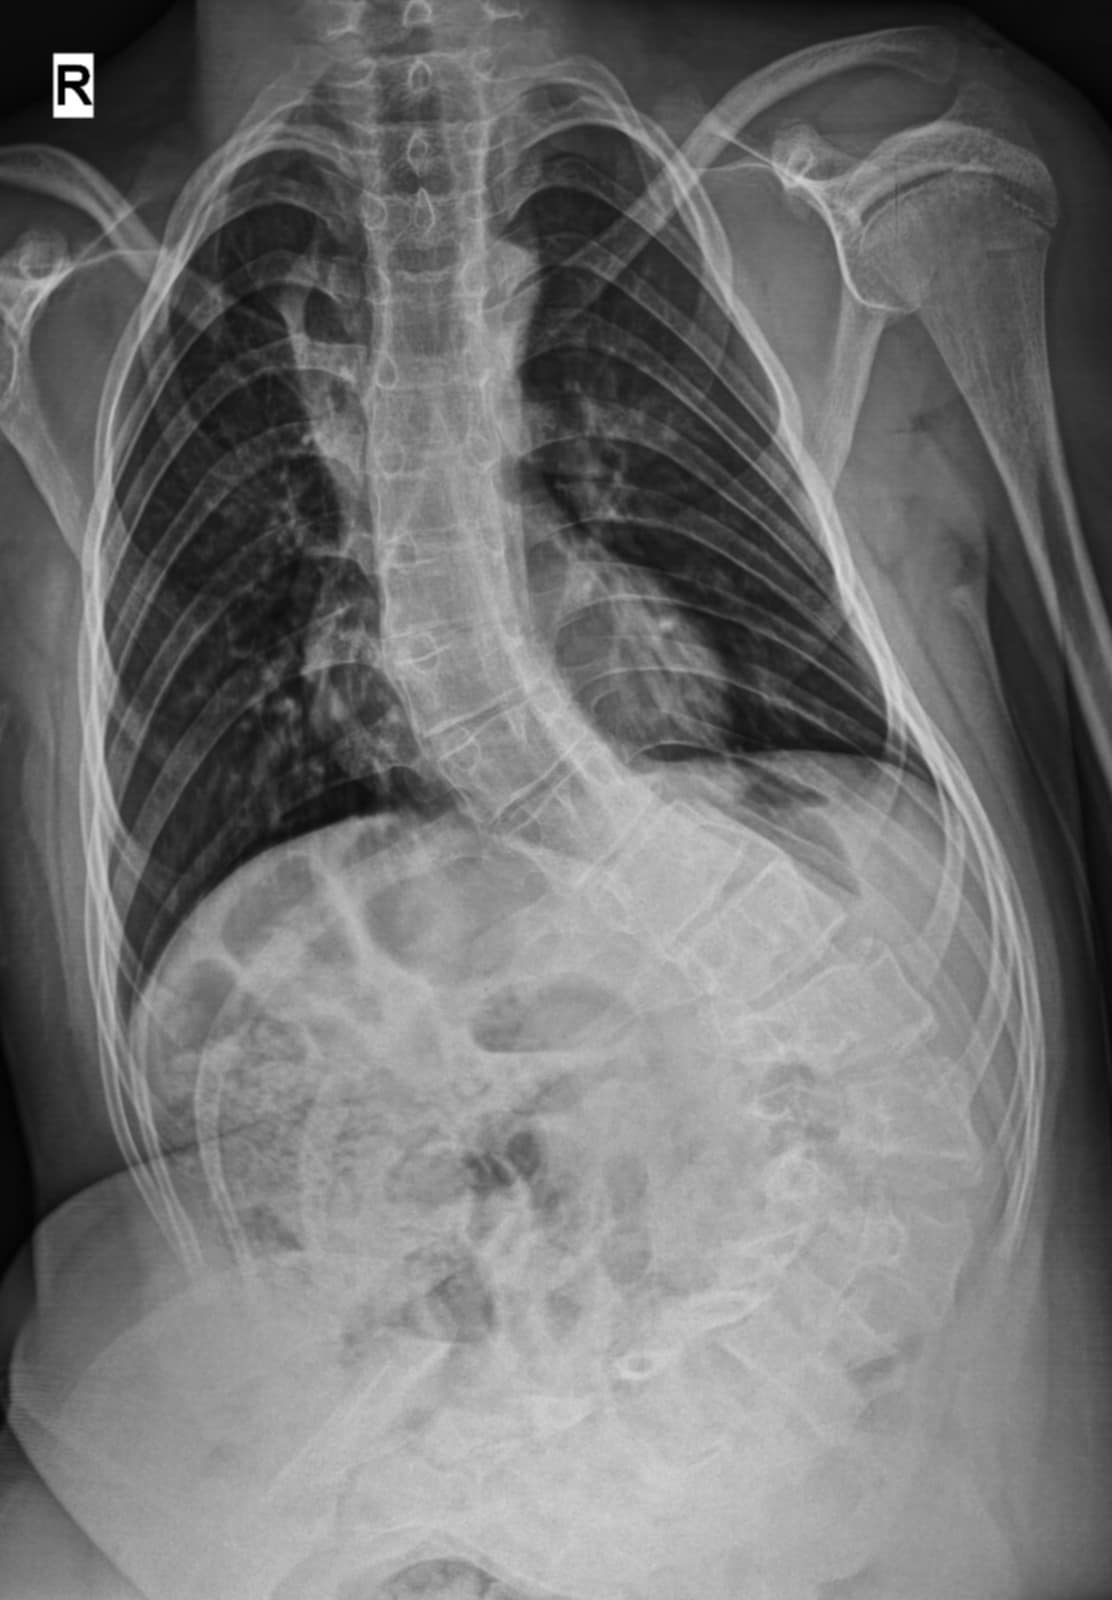

Băiatul a fost diagnosticat cu scolioză severă cu unghi Cobb de 100 grade